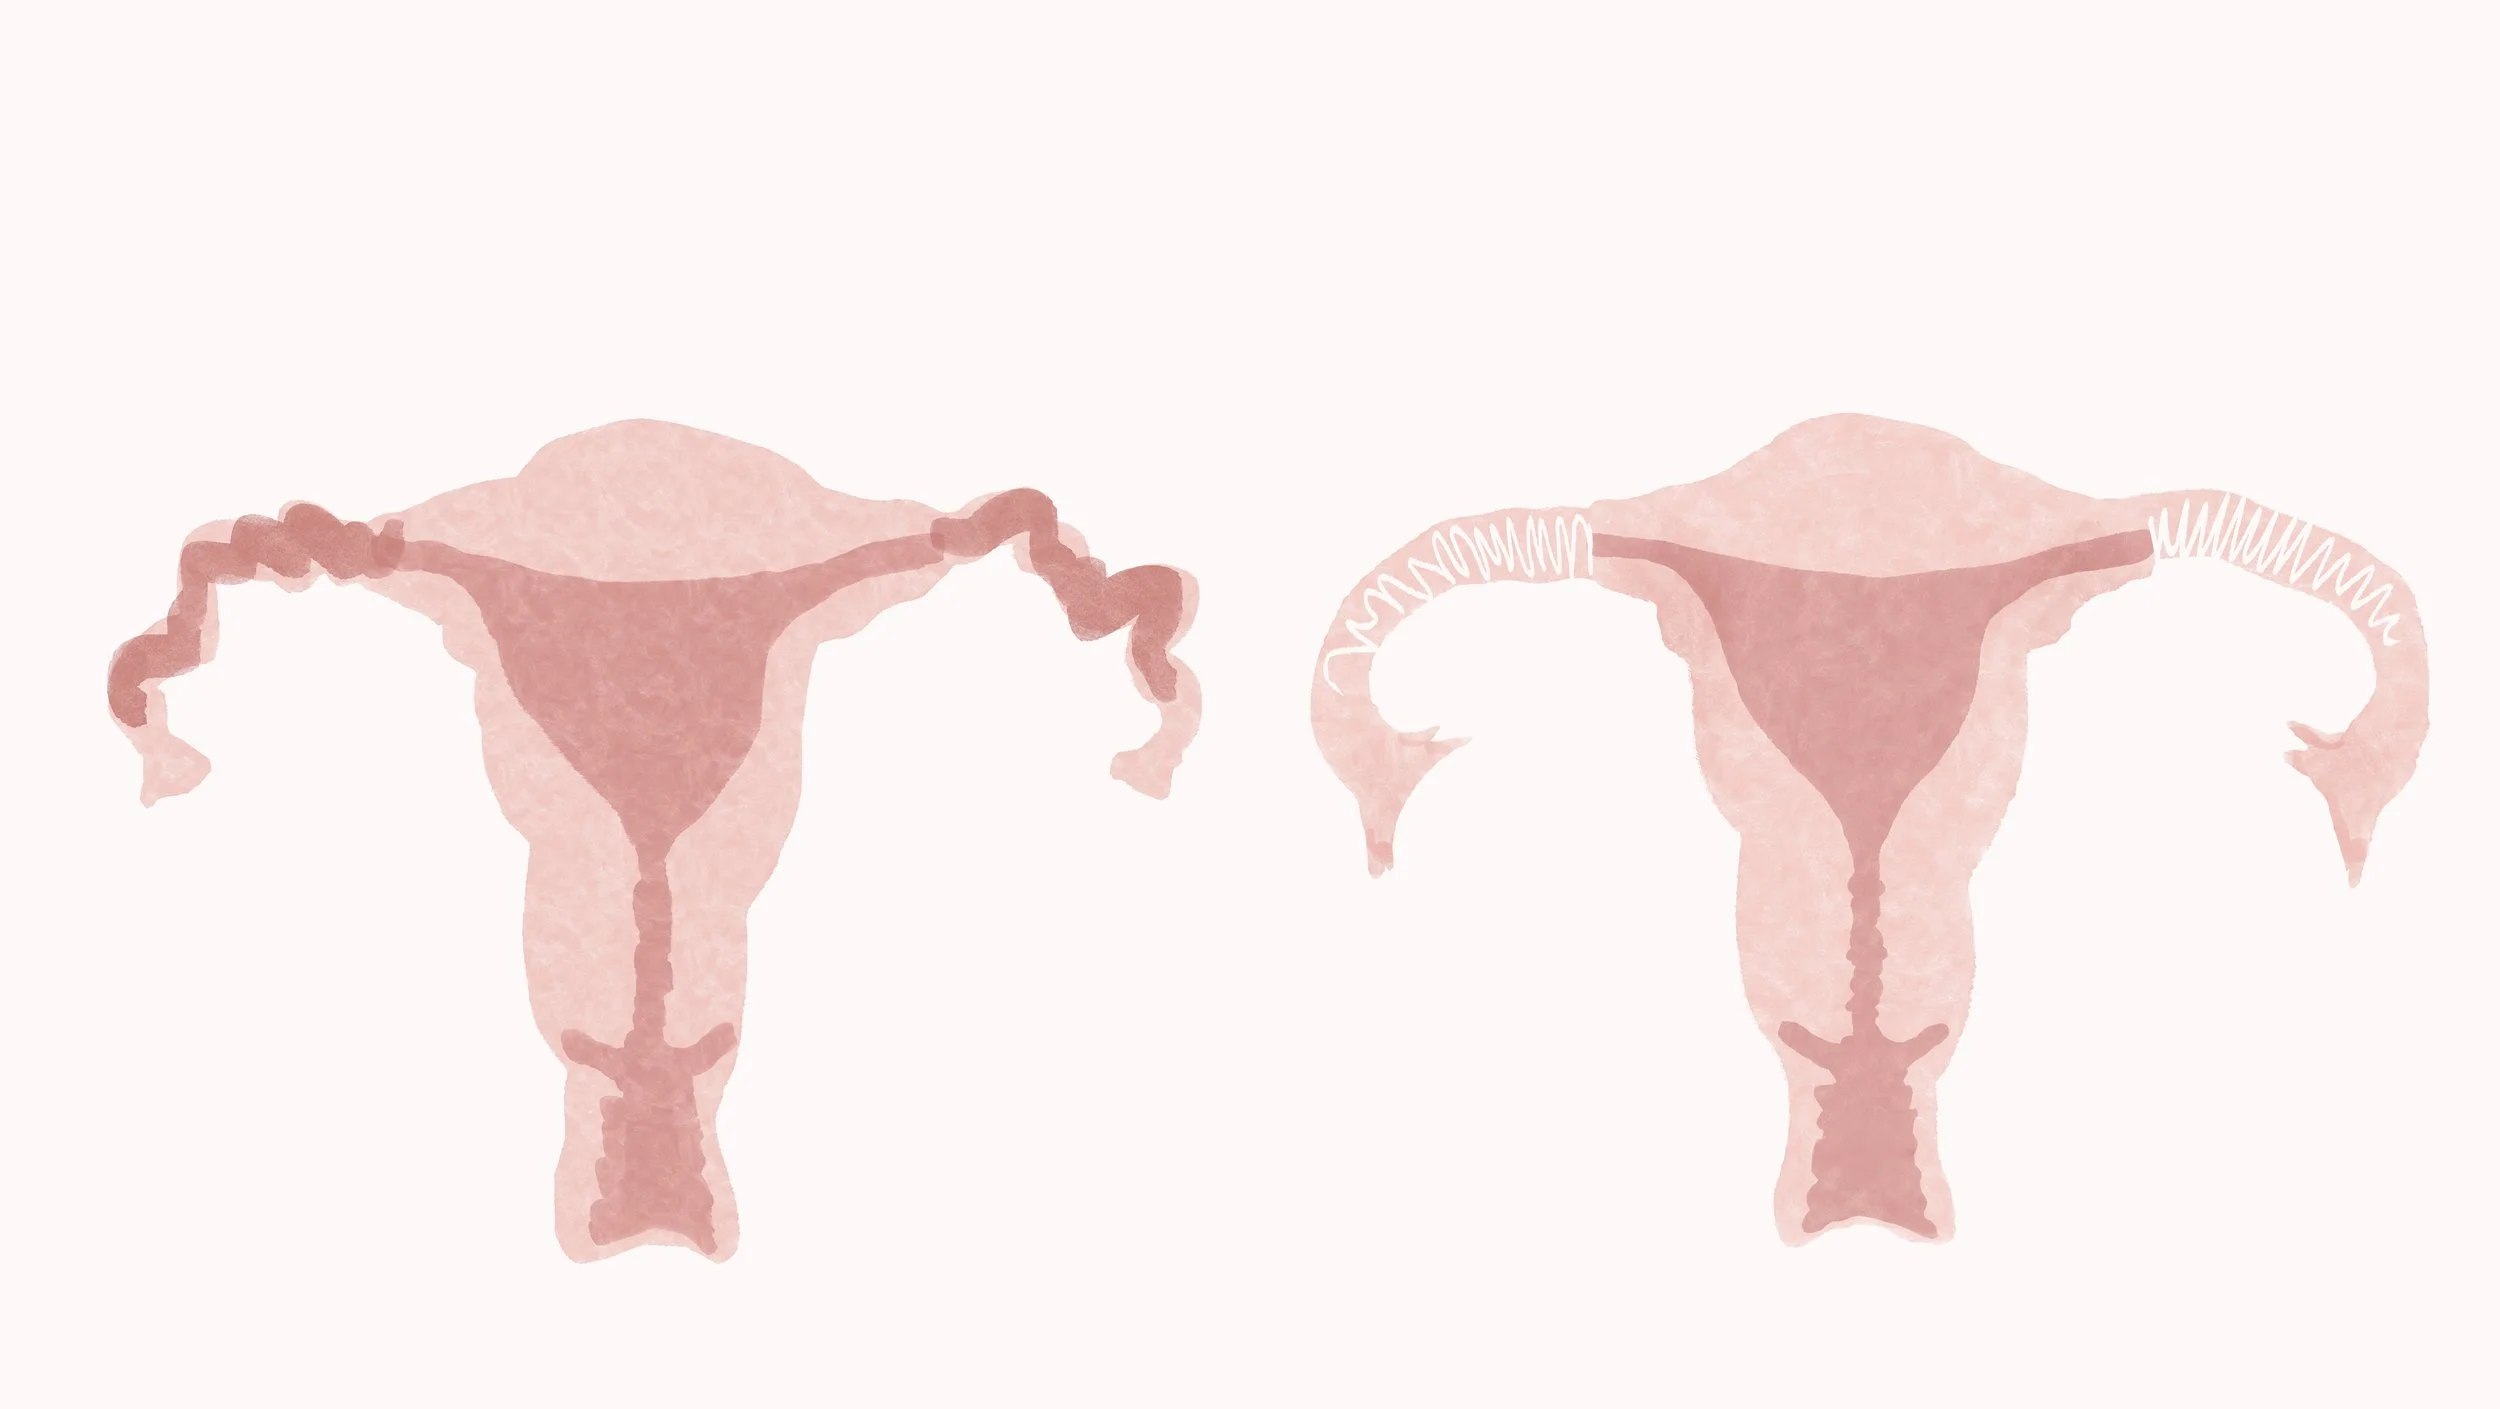

Uterine Malformations

Hysterosalpingogram (HSG)